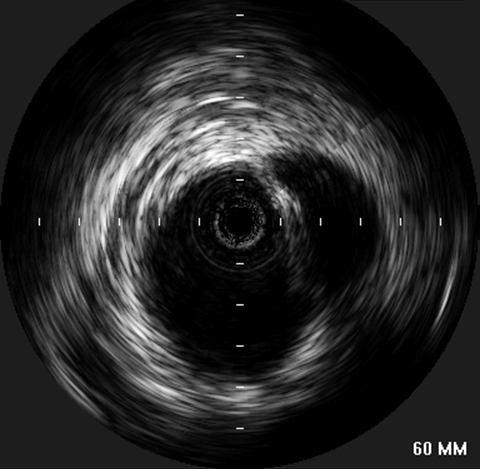

| Figure 4: “Completion”-IVUS examination showing exclusion if the proximal descending aorta. |

concerns about myocardial contusion. After lowering the systolic blood pressure to 100 mmHg, the stent graft was deployed precisely distal to the left common carotid artery. Small boluses of contrast were administered during deployment to confirm device position relative to the left carotid artery. A completion aortogram confirmed adequate exclusion of the transected area and no evidence of an endoleak was identified. A completion IVUS exam was performed, showing complete apposition of the device to the aortic wall circumference (Figure 4). Subsequently, the catheters and the wire were removed from the left groin, and the left common femoral artery is repaired under direct vision. The patient was found to have bounding distal pulses and was neurologically intact after the procedure. The pulses of the left arm were detectable with Doppler. Although the systolic blood pressure in the left arm decreased by 30 mm Hg, the patient did not demonstrate any ischemia or claudication symptoms.